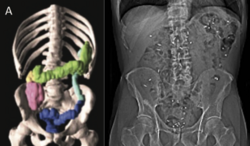

CT scanning of the abdomen

Every morning for 6 days a capsule containing 10 very small plastic markers, which the intestine cannot absorb, is ingested. The number of remaining markers in the intestine on the day of the scan can be converted into transit time through the gastrointestinal tract. This is thus a measure of intestinal function and particularly intestinal peristalsis (intestinal movements). Likewise, on this scan, the volume of the colon can be analysed as another measure of intestinal function and constipation.

Every morning for 6 days, a capsule containing 10 very small plastic markers (radiopaque) is ingested. The plastic markers cannot be absorbed from the intestines. The number of retained markers in the intestines reflects the intestinal transit time. Many patients with PD display increased intestinal transit time, which is an objective marker of constipation.